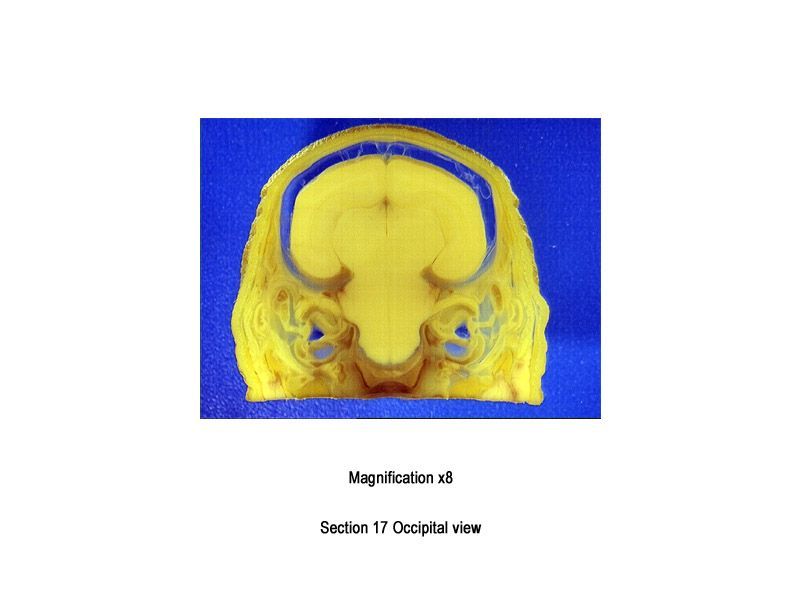

The images below show the normal appearance of Bouin's fluid fixed head sections in specimens at Day 29 of gestation (day mating observed = Day 0).

It is essential that both sides of each section is examined so that structures that exist is several sections can be visualised by the examiner in their mind as 3D.